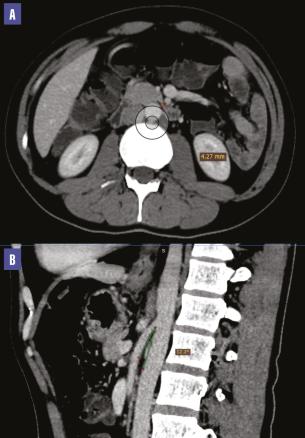

Une tomodensitométrie (TDM) abdominale met en évidence une compression de la troisième portion du duodénum par l’artère mésentérique supérieure associée à une importante dilatation de l’estomac et des deux premières portions du duodénum. L’angle aortomésentérique est mesuré à 12,2° et la distance aorte-artère mésentérique supérieure atteint 4,27 mm (fig. 1 et 2 ), ce qui a permis de poser le diagnostic du syndrome de la pince aortomésentérique.

Une tomodensitométrie (TDM) abdominale met en évidence une compression de la troisième portion du duodénum par l’artère mésentérique supérieure associée à une importante dilatation de l’estomac et des deux premières portions du duodénum. L’angle aortomésentérique est mesuré à 12,2° et la distance aorte-artère mésentérique supérieure atteint 4,27 mm (